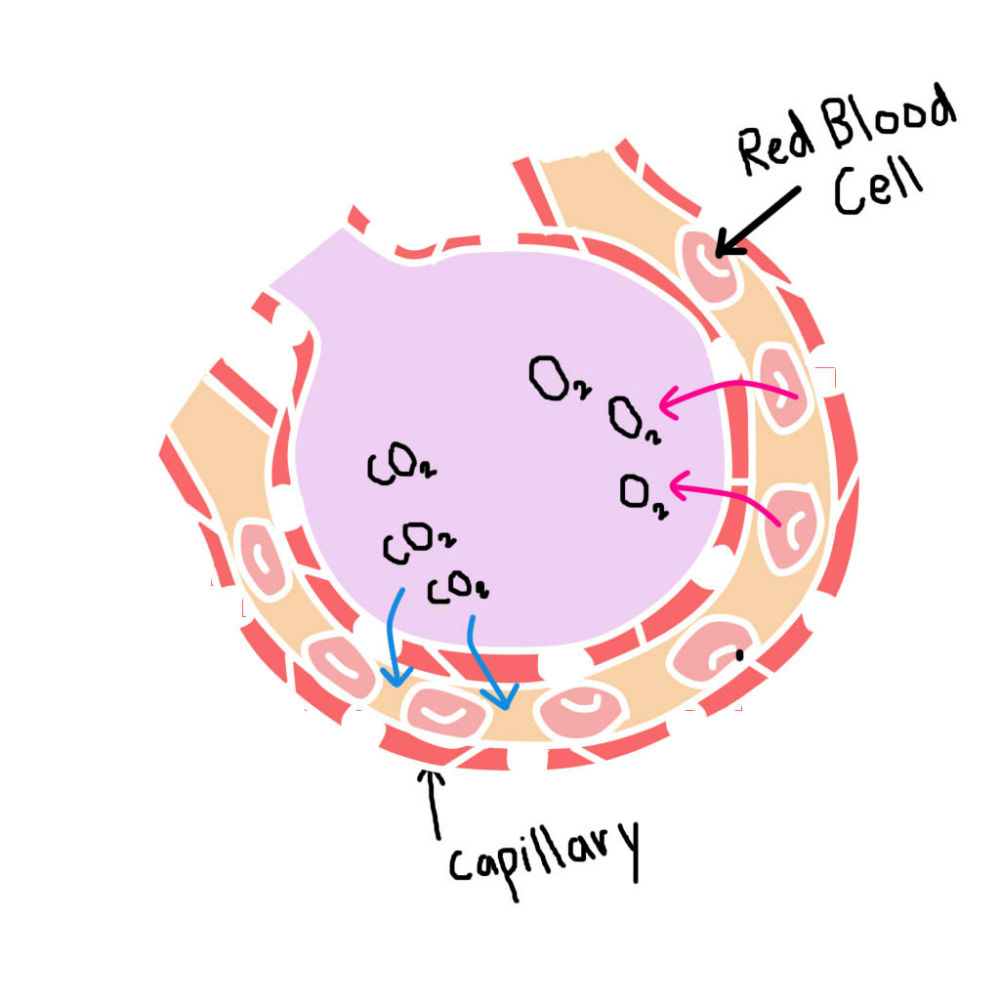

ระบบไหลเวียนโลหิต ทำหน้าที่อะไร และมีส่วนประกอบสำคัญอะไรบ้าง

37,900+ การไหลเวียนของเลือด ภาพถ่ายสต็อก รูปภาพ และภาพปลอดค่าลิขสิทธิ์ … หัวใจกับการไหลเวียนของเลือด – ระบบไหลเวียนโลหิต

หัวใจกับการไหลเวียนของเลือด – ระบบไหลเวียนโลหิต ม.2 ระบบหมุนเวียนเลือด | Science – Quizizz

ม.2 ระบบหมุนเวียนเลือด | Science – Quizizz ระบบไหลเวียนเลือด: หัวใจ

ระบบไหลเวียนเลือด: หัวใจ รูปภาพประกอบระบบไหลเวียนโลหิตของร่างกายที่วาดด้วยมือ PNG , ร่างกาย …